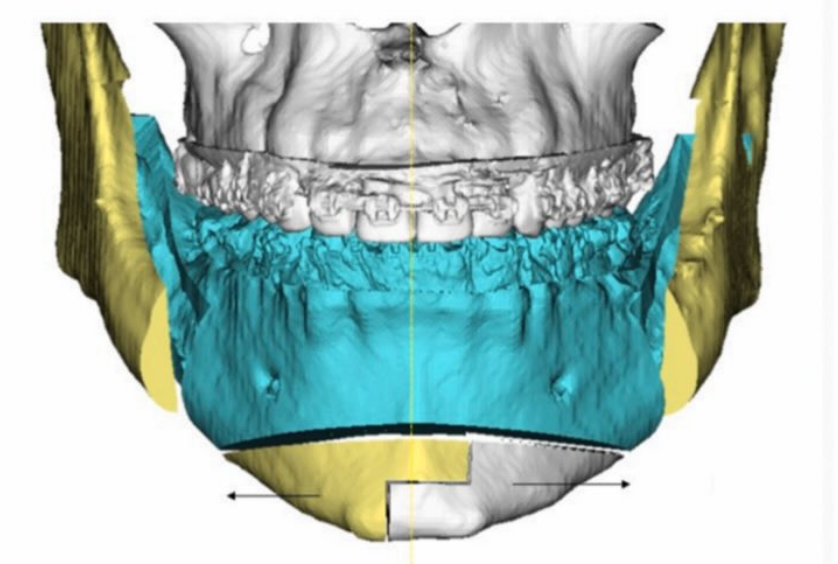

Just finished up this case and sent it to production.

-About 8mm right and 10mm left widening on jaws.

-Both sides of jaw about 4.5mm height added.

-Concavity to jaw shape added/fixed.

-3.1mm saddle.

There will be a genioplasty as well.

Old silicone wraparound:

Old silicone wraparound: